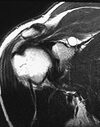

A, Normal infraspinatus muscle (arrow). B, Fatty infiltration of the infraspinatus muscle (arrow).